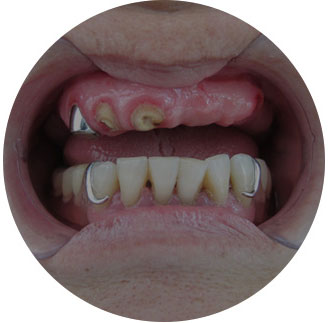

可以解决全口、半口无牙颌、 牙槽骨严重萎缩/极薄问题。